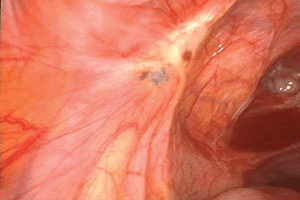

Figure 10 : Une endométriose biologiquement active du ligament large gauche est associée à des épaisses lésions cicatricielles jaunâtres et à du sang emprisonné sous la surface du péritoine (en rétropéritonéal). L’uretère se trouve au-dessous de la lésion.

Figure 11 : Une exérèse agressive radicale de la lésion montrée dans la figure 10 requiert une urétérolyse. L’uretère gauche (flèche) était atteint par une légère fibrose rétropéritonéale qui s’était étendue depuis le nodule fibreux péritonéal (à l’intérieur du cercle).